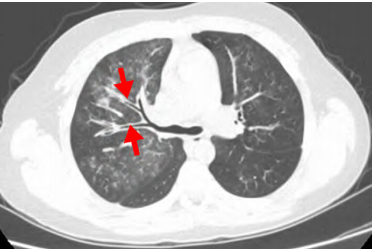

肺炎支原体感染症状以发热、咳嗽等为主要症状,一般咳嗽比较剧烈,而且在退热后咳嗽还可能持续1-2周,可同时伴有头痛、流涕、咽痛等症状。肺部早期体征不明显,随着病情进展可出现呼吸音降低和干、湿啰音。